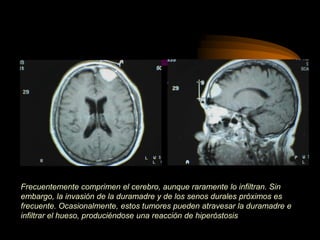

Frecuentemente comprimen el cerebro, aunque raramente lo infiltran. Sin

embargo, la invasión de la duramadre y de los senos durales próximos es

frecuente. Ocasionalmente, estos tumores pueden atravesar la duramadre e

infiltrar el hueso, produciéndose una reacción de hiperóstosis

Frecuentemente comprimen elcerebro, aunque raramente lo infiltran. Sin embargo, la invasión de la duramadre y de los senos durales próximos es frecuente. Ocasionalmente, estos tumores pueden atravesar la duramadre e infiltrar el hueso, produciéndose una reacción de hiperóstosis